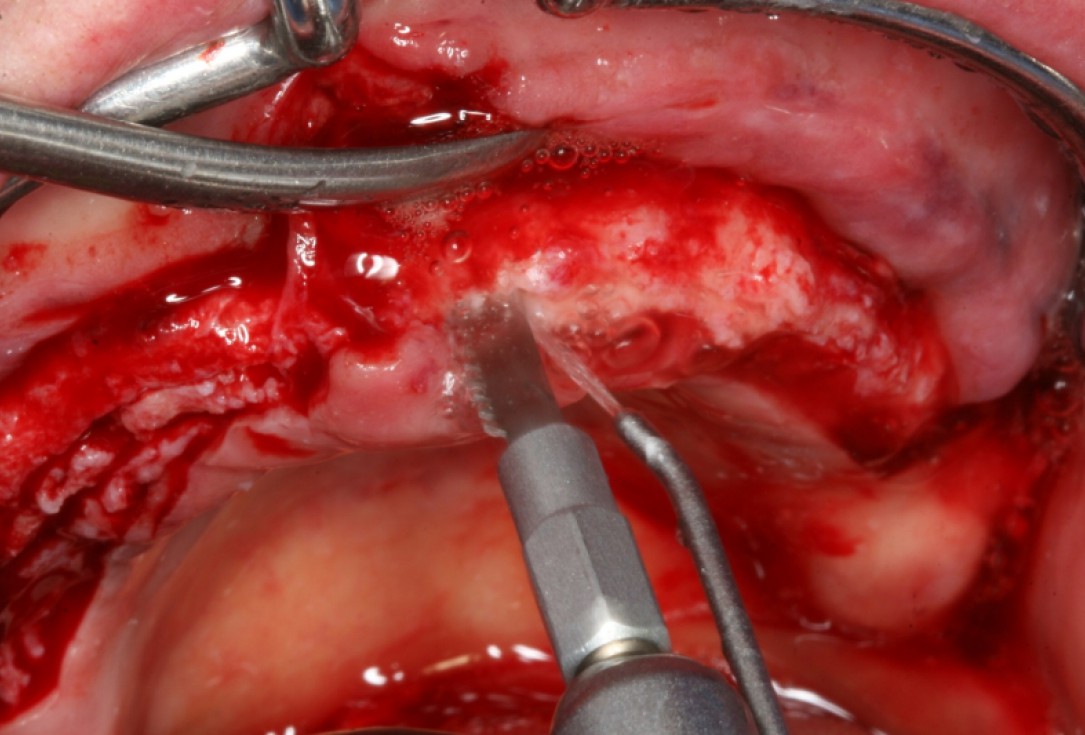

02/10 - Deep bone splitting with oscillating saw in regio 15 to 25Circular bone splitting with maxresorb® & collprotect® membrane - PD Dr. J. Neugebauer